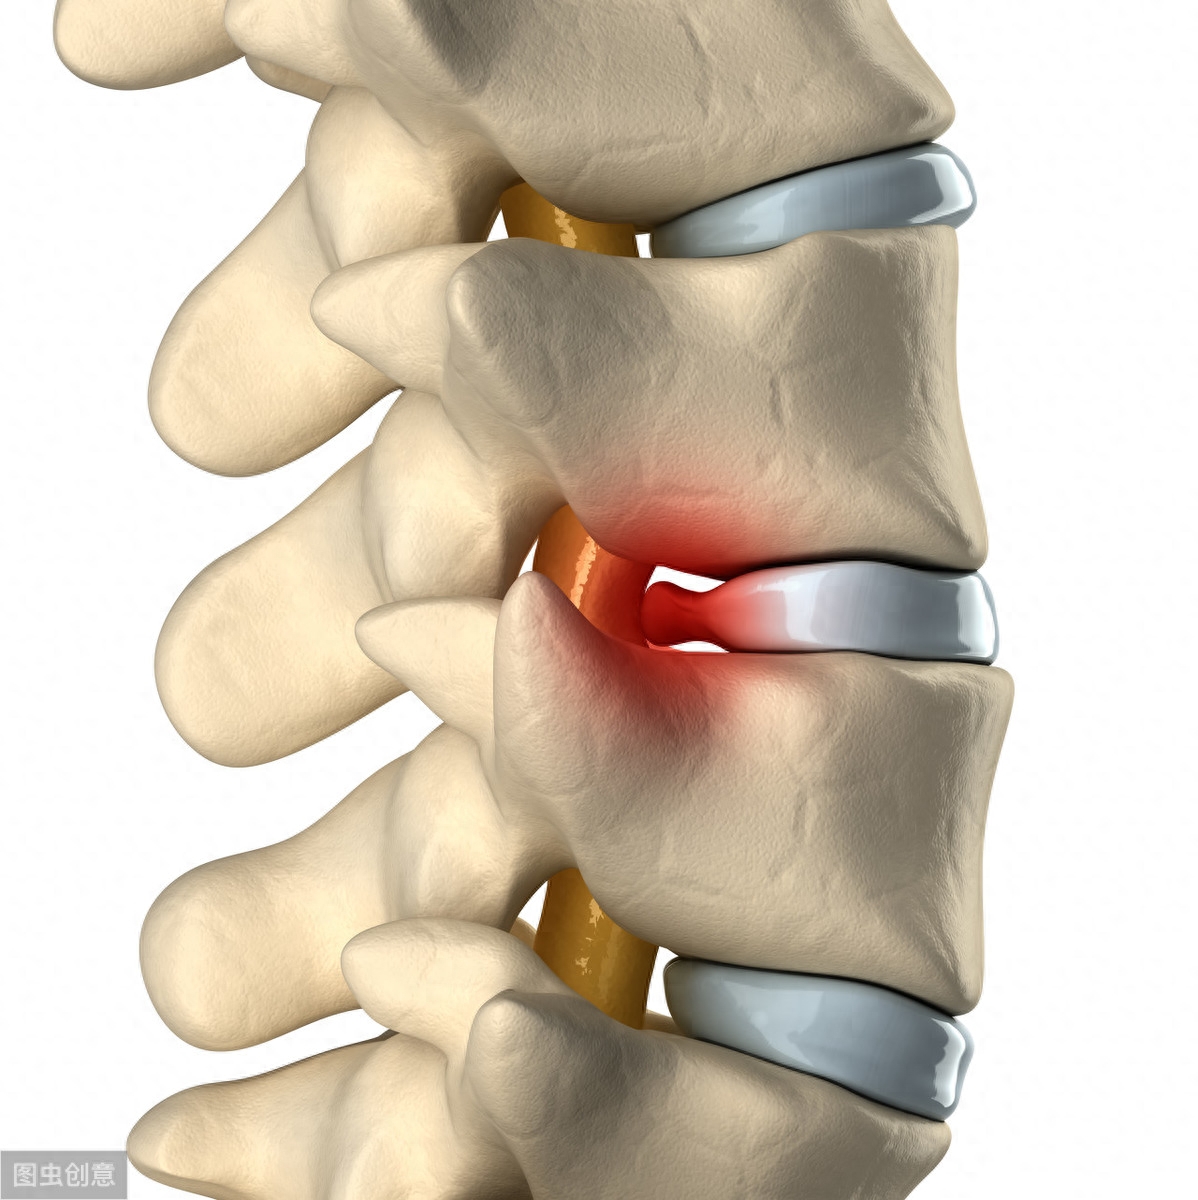

腰椎间盘突出——腰部的椎间盘容易“出轨”

腰椎间盘是什么?

人体的脊柱是由椎间盘连着椎体,外面用强大的肌肉和韧带做支撑形成的坚强结构。

而椎间盘就夹在两段椎骨中间,像一块圆圆的软垫,避免两块椎骨直接碰撞和摩擦。

这块软垫又像夹心巧克力,有着较硬的外壳和软心,即纤维环和髓核。

椎间盘在人体中有三个重要作用:一是维持椎体关节稳定,保持脊柱的正常活动度;二是调节脊柱的顺应性;三是缓冲震动和降低脆性。

人体共有23块椎间盘,分布于颈椎、胸椎和腰椎,而位于腰部的椎间盘最容易发生突出。

椎间盘突出主要是由于椎间盘的纤维环破裂,髓核被挤压出来,就像是巧克力外壳破了,软心流了出来,就像是椎间盘“出轨”了。

脱出的髓核会刺激周围的神经,突出的椎间盘也会压迫神经,致使腰痛、腿痛、腿麻、无力。

但腰椎间盘突出不一定就会引起腰痛,只有10%~15%的腰腿痛是腰椎间盘突出症造成的。

有腰腿痛症状的叫腰椎间盘突出症;没症状的叫腰椎间盘突出,两者是不同概念。